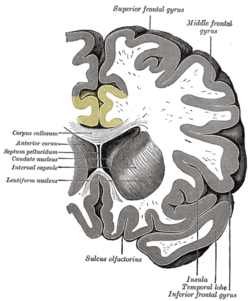

القشرة الحزامية cingulate cortex، تعرف أيضاً بالقشرة الحوفية، هي جزء من المخ يقع في الجانب الإنسي من القشرة المخية. القشرة الحزامية تشمل التلفيف الحزامي بأكمله، والذي يقع فوق الجسم السفني مباشرة، ويستمر حتى التلم الحزامي. القشرة الحزامية عادة ما تعتبر جزءاً من الفص الحوفي.